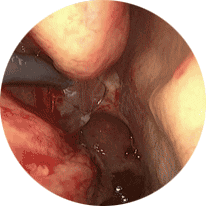

정확한 내시경 기반의 안전한 시술

내시경으로 필요한 부위만 정확히 냉동해 안전성과 효과를 높였습니다.